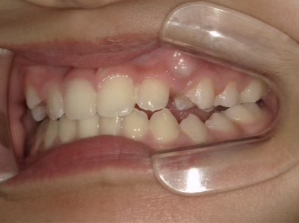

治療前① 小1:6y8m 初診

| カウンセリング・診断結果 | 前歯の生え変わり時期に来院されました。(写真①) 乳歯列期に受け口の既往があり切端咬合になりそうなため、受け口に対する矯正治療の考え方と対処法、当院のコンセプトを説明したところ治療を希望されたので診断を行いました。 診断の結果、上顎骨に対し下顎骨が長く、骨格的な構造も下顎突出型反対咬合(下顎骨が適切な位置よりも前に出ているタイプの受け口)と分かりました。 顔立ちは、中顔面が引っ込んだように見えるコンケーブに移行中です。 機能的な問題として低位舌があるため受け口の悪化が考えられることも説明し、以下の治療を提案しました。 |